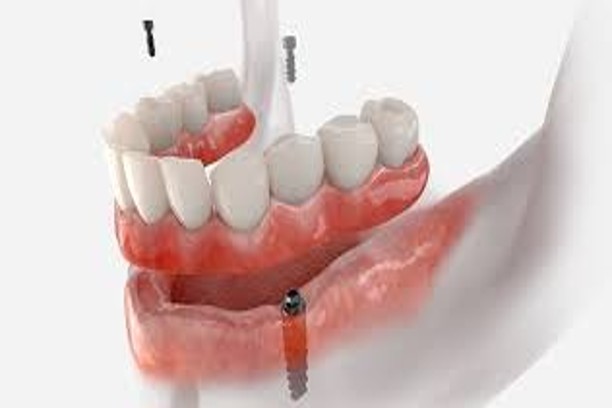

Pre-Prosthetic Surgery

Preparatory procedures to create a strong foundation for dental prosthetics.